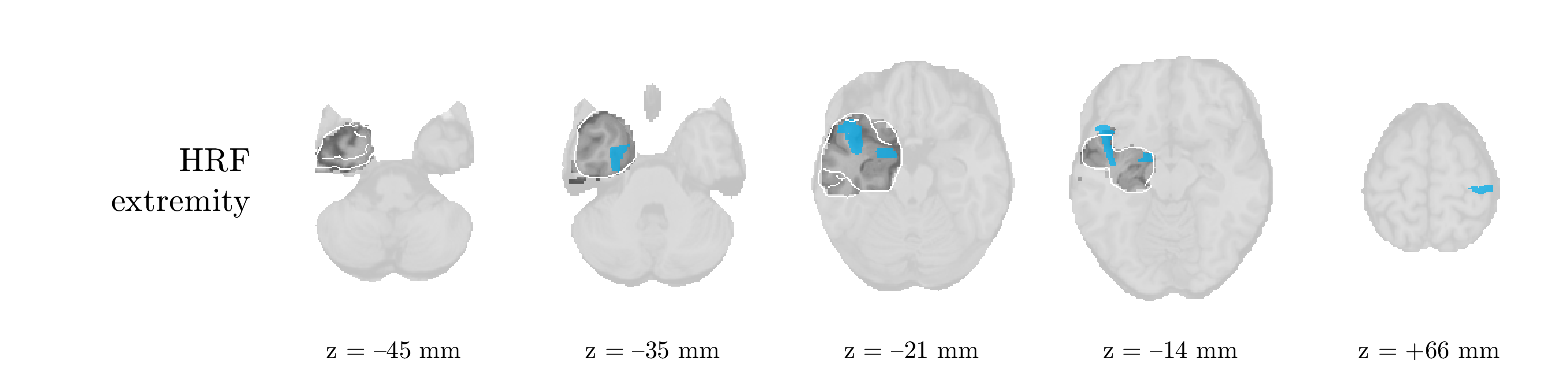

Patient 1

We analyze the solution with sources. Figure 1 shows the EEG signatures and HRF waveforms. One of the sources is highly correlated to the MWF reference (in grey), which was already known from Table B.3. This IED-related source had a typical low-frequency spectrum, which is expected for the typical spike-and-wave interictal discharges. The topography is relatively diffuse, although the highest amplitudes are mostly in the left hemisphere. This is in accordance with the lateralization of ictal onset zone (left temporal lobe, cfr. Table 1). There are some noteworthy observations to be made about some of the other components. The fourth has an unusually sharp spectrum, is mainly localized on two nonadjacent center electrodes, and is sustained for a single period of many seconds Hence, this component likely captured an artifact (of yet unknown origin), although we spotted no large-amplitude changes in the EEG itself. Similarly, the third source is only present at one frontal electrode, and exists in a frequency range above 20 Hz. It might represent a muscle artifact, e.g., due to frowning or twitching of some muscles in the forehead. The HRFs of all ROIs are shown in Figure 1(b). Two of the basis functions seem to have converged to a very similar waveform, which is an unfortunate possibility if two initial HRFs are too close to the same local optimum in their respective parameters. This reduces the expressive power of the basis set, which is clearly visible, since many ROIs have a nearly identical HRF. One of the twenty ROIs with the highest-entropy HRF overlapped the IOZ, although clearly this HRF (bold line) is not among the most dissimilar waveforms for this patient. This is also visible in Figure 2: both the HRF entropy and extremity maps show a small overlap with the delineated IOZ. Despite the good correspondence in the EEG domain, no significant (de)activation of the IED-component is found inside the IOZ.